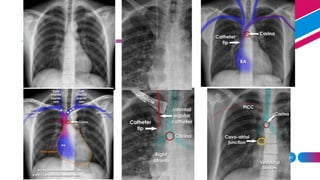

• For optimal dilution- tip should

carina on a chest radiograph

• Short term- At carina

• Long term/ hemodialysis-cavo-

atrial junction (2 vertebral bodies

below carina )